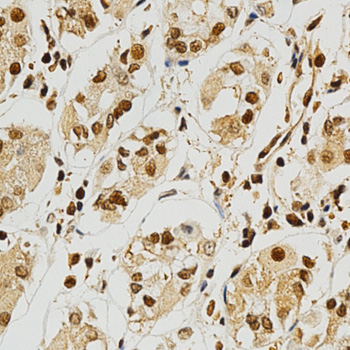

Immunohistochemistry of paraffin-embedded human stomach using NFATC1 antibody at dilution of 1:200 (x400 lens).